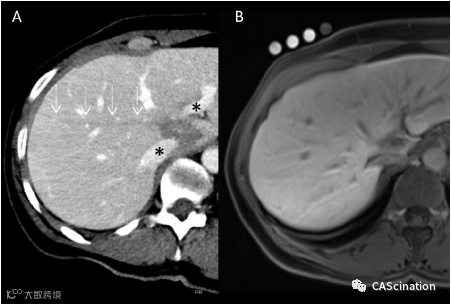

3个月和6个月随访期的钆酸盐增强MRI显示介入治疗后的变化,同时考虑到对比剂动态和扩散加权成像的磁共振序列,没有任何残留肿瘤痕迹,对比剂细胞内摄取减少(图3B)。

图3–在消融后的CT对照扫描中,病灶完全覆盖,左门静脉分支和主肝静脉未受损(A,*号)。经肝穿刺路在针收缩过程中通常采用小能量治疗,以防止肿瘤细胞扩散。在消融后的对照扫描中可以很清楚地看到凝血通路(A,虚线箭头)。6个月的肝胆相中使用钆酸盐的MRA随访显示尾状叶有轻微的收缩疤痕。